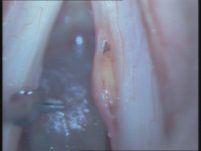

ציסטה במיתרי הקול נגרמת מהצטברות כיס של נוזל בתוך המיתר כתוצאה מחסימה פנימית. אם הציסטה עמוקה, המיתר נהיה עבה יותר ונוקשה. ציסטה משפיעה על הקול באותה צורה כמו פוליפ או יבלת.

באיור: ציסטה במיתר הקול